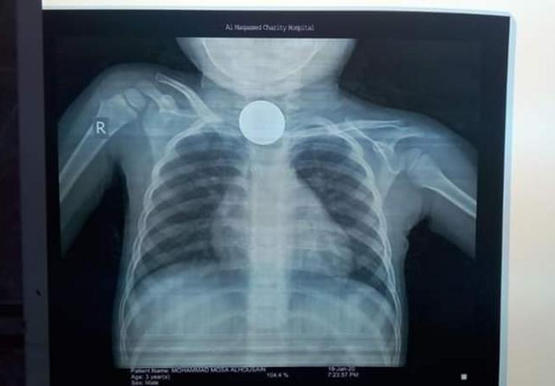

| إنقاذ حياة طفل بلع قطعة نقدية بعمان |

اسعف إلى مستشفى المقاصد الخيرية التابع لصندوق الزكاة طفل عمره اربع سنوات قام بابتلاع قطعة نقدية معدنية.حيث تم على الفور التعامل مع الحالة وادخالها على غرفة العمليات.وقام... |